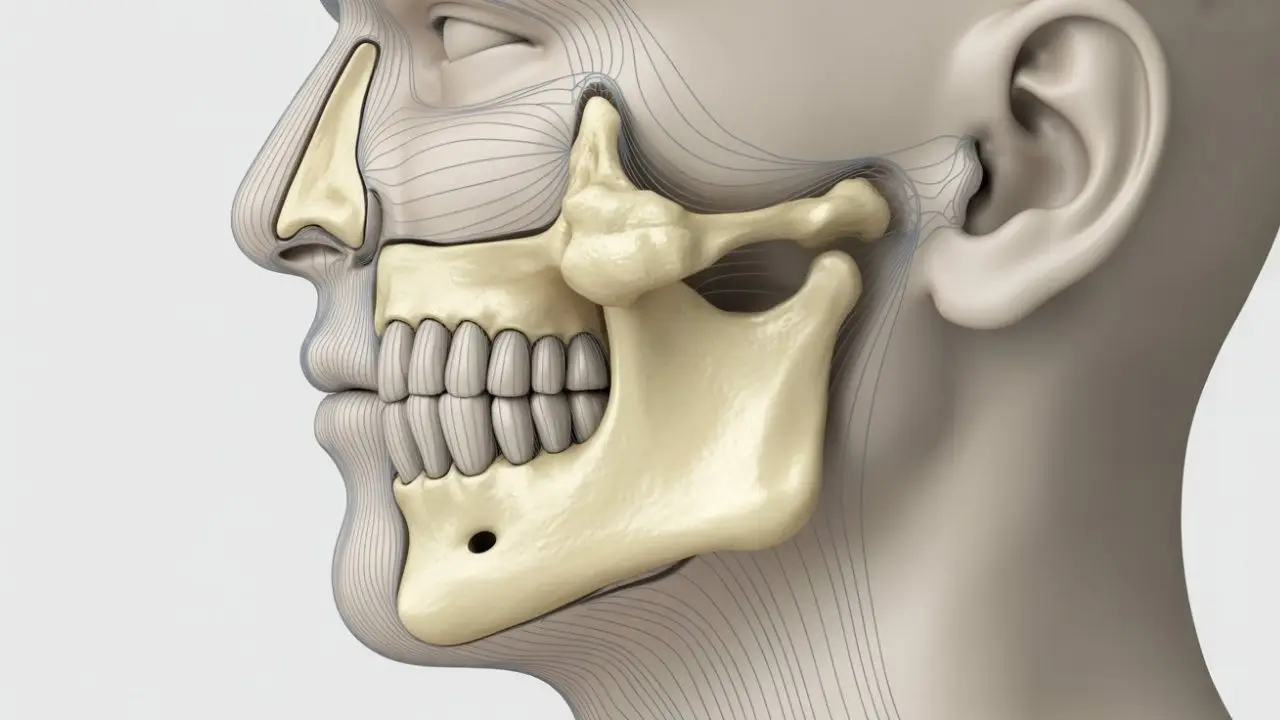

Understanding the Temporomandibular Joint

The temporomandibular joint is one of the most complex joints in the human body. It allows both hinge-like and sliding movements, enabling the jaw to move up and down, side to side, and forward. Because of this complexity, the joint is vulnerable to stress, injury, and muscular imbalance.

Temporomandibular disorders refer to a group of conditions that affect the temporomandibular joint, the muscles responsible for jaw movement, or both. The TMJ connects the lower jaw (mandible) to the skull and plays a crucial role in speaking, chewing, yawning, and facial expressions.